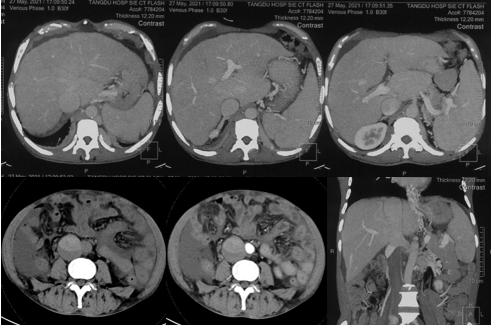

6月20日,患者及家屬懷揣著忐忑的心情來到西安國(guó)際醫(yī)學(xué)中心醫(yī)院找到韓國(guó)宏教授,韓教授詢問病情后閱患者外院CT片,明確診斷布加綜合征,同時(shí)發(fā)現(xiàn)了一個(gè)新的問題,在詢問病史時(shí)了解到患者近一周雙下肢乏力伴腫脹明顯加重,遂立即安排了急診CT,證實(shí)下腔靜脈內(nèi)急性血栓形成!

6月22日,在韓國(guó)宏教授的帶領(lǐng)下,患者于消化介入診療中心行下腔靜脈開通術(shù)。術(shù)中可見:下腔靜脈全段擴(kuò)張,膜性閉塞,腎靜脈平面以下可見血栓形成并伴有粗大的側(cè)枝靜脈,遂對(duì)狹窄段球囊擴(kuò)張并植入支架,術(shù)后下腔靜脈血流通暢,側(cè)枝消失。術(shù)后第2天,患者腹壁靜脈曲張幾乎消失不見,走路也輕快了許多。明明只是薄薄的一層膜,為什么開通起來這么難?韓教授指出,盡管布加綜合征介入開通技術(shù)已使創(chuàng)傷降到了最低,但受到患者個(gè)體差異及醫(yī)療水平參差不齊的限制,仍有可能出現(xiàn)嚴(yán)重的并發(fā)癥,主要包括:心包積血、縱隔血腫、心包填塞甚至下腔靜脈撕裂引起的大出血等。而其發(fā)生率與術(shù)者的操作熟練程度及經(jīng)驗(yàn)有很大的關(guān)系。